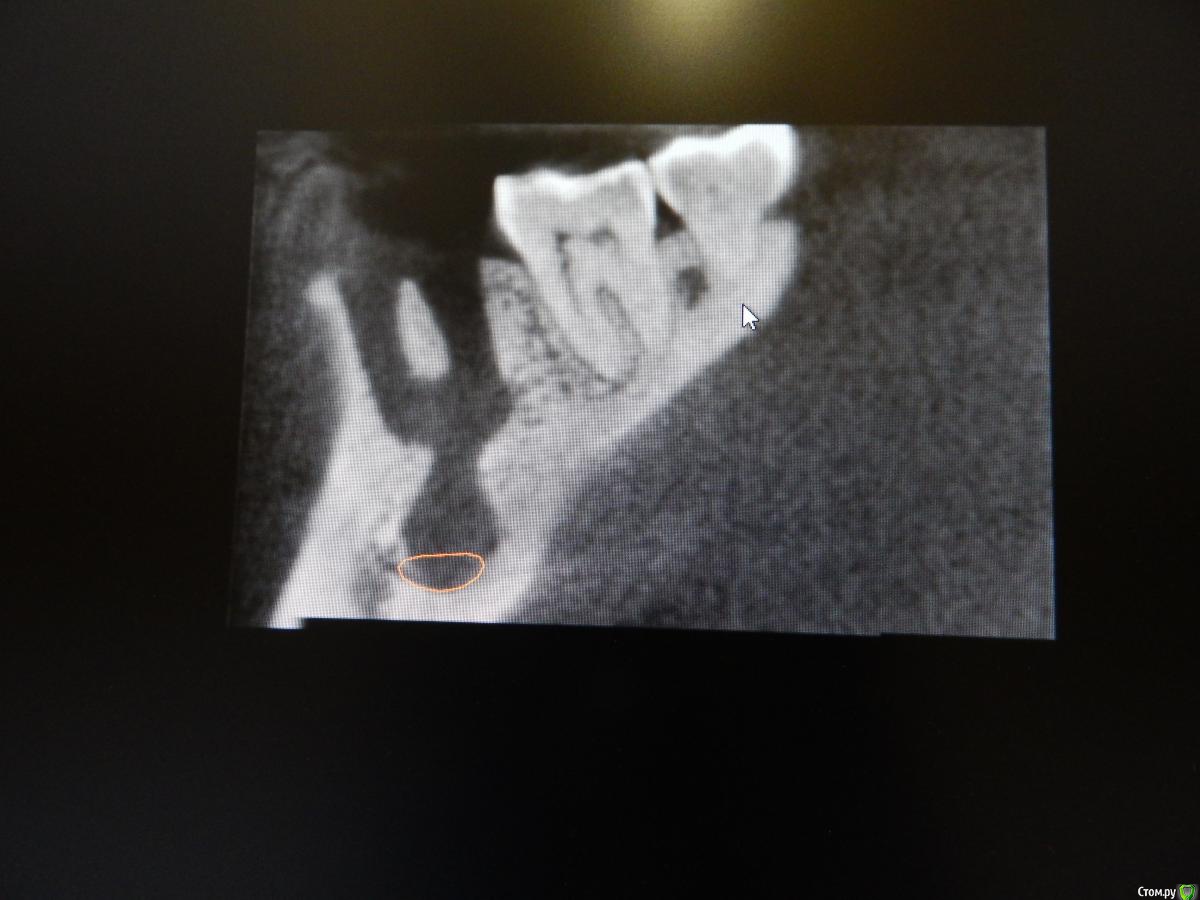

dantist_movani Опубликовано 8 октября, 2015 Поделиться Опубликовано 8 октября, 2015 Пациент обратился более 2 месяцев назад с жалобами на боли при накусывании, постоянные ноющие боли в зубе 3.6. Со слов больного зуб болел и ранее, но спасали НПВС, а тут 3 дня не может уснуть. Ранее зуб лечился (резорцин-формалиновый метод), перкуссия положительная, по переходной складке всё спокойно, лимфоузлы слева(поднижнечелюстные) чуть увеличены, при пальпации болезненны. Удалил, кюретаж, отделяемого никакого, под сгустком лунка зажила. Интраоральный снимок, делался в 2011 году, но зуб тогда болеть перестал. КТ на следующий день после удаления. Радикулярная киста? Какой план действий в данной ситуации? Ссылка на комментарий

dantist_movani Опубликовано 8 октября, 2015 Автор Поделиться Опубликовано 8 октября, 2015 ждем 3 месяца. потом им ждем 3 месяца. потом имплант.имплантат конечно хорошо, но меня пока волнует деструкция костной ткани! особенно то, что может быть вовлечен н/ч нерв Ссылка на комментарий

Чертков Александр Опубликовано 8 октября, 2015 Поделиться Опубликовано 8 октября, 2015 Ничего там не вовлечено! Рентген контроль через пару месяцев (желательно КТ) и болтокрутинг. 1 Ссылка на комментарий

diesel87 Опубликовано 8 октября, 2015 Поделиться Опубликовано 8 октября, 2015 Меня больше волнует как перегородка в воздухе висит.... 5 Ссылка на комментарий